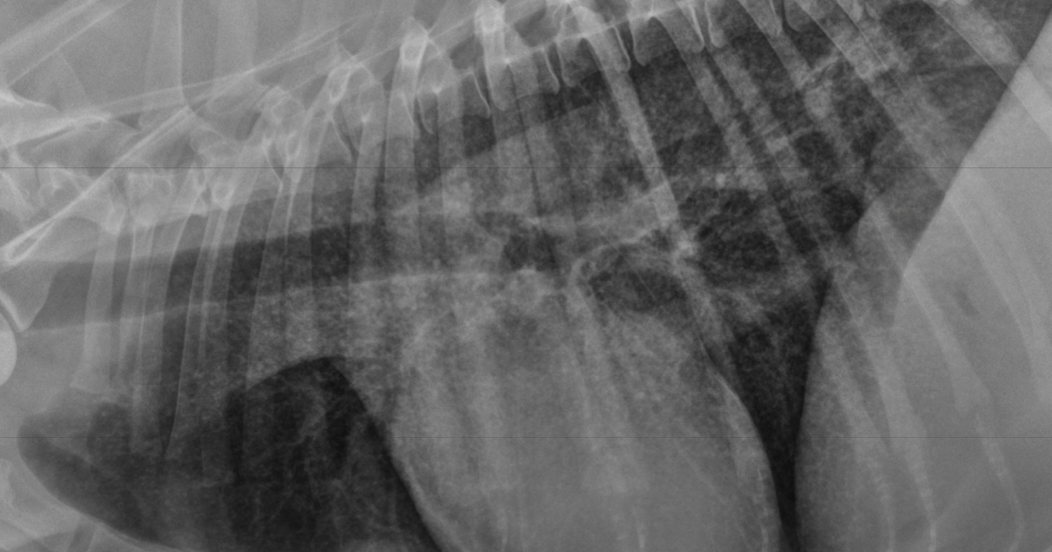

what kind of pattern

normal- left

interstitial- right